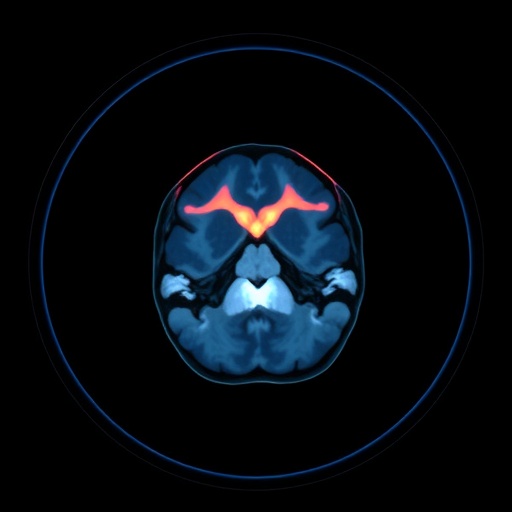

In a groundbreaking study set to be published in the esteemed journal Pediatric Radiology, a team of researchers led by Aldraihem et al. has unlocked significant advancements in the realm of infant magnetic resonance imaging (MRI). This pioneering work explores the efficacy of a Deep Learning-assisted feed-and-wrap technique as a compelling alternative to traditional general anesthesia for infants under 4 months. The implications of this research could be transformative, changing how pediatric care professionals approach imaging in very young patients.

The research team utilized state-of-the-art deep learning algorithms in their feed-and-wrap technique. By employing these advanced computational methods, they were able to analyze real-time imaging data, ensuring optimal positioning and minimal movement during MRI scans. This deep learning model was trained on a vast dataset, allowing it to predict the ideal wrap position that minimizes infant motion while delivering high-quality images akin to those obtained under anesthesia.

The feed-and-wrap technique works by using specialized fabric and calming strategies to soothe infants, promoting a state of stillness conducive to clearer imaging. This method capitalizes on the natural calming mechanisms of swaddling while integrating technology to further enhance patient compliance. The novelty lies in how deeply integrated technology can alleviate the need for anesthesia, which is particularly significant for vulnerable populations like infants.